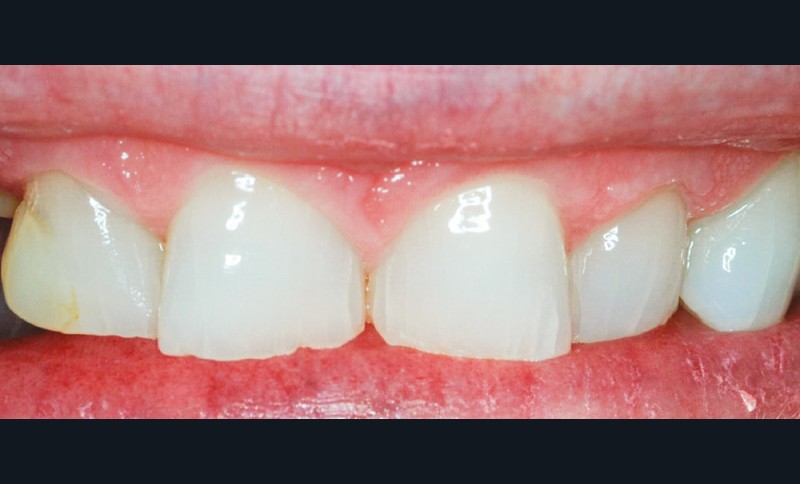

Même en l’absence de restauration, l’espace biologique n’est parfois naturellement pas correctement établi sur la dent. Ce phénomène est couramment décrit comme une éruption passive retardée. Elle peut être une indication d’élongation coronaire esthétique afin de rétablir la couronne clinique dans son intégralité (fig. 2a-c).